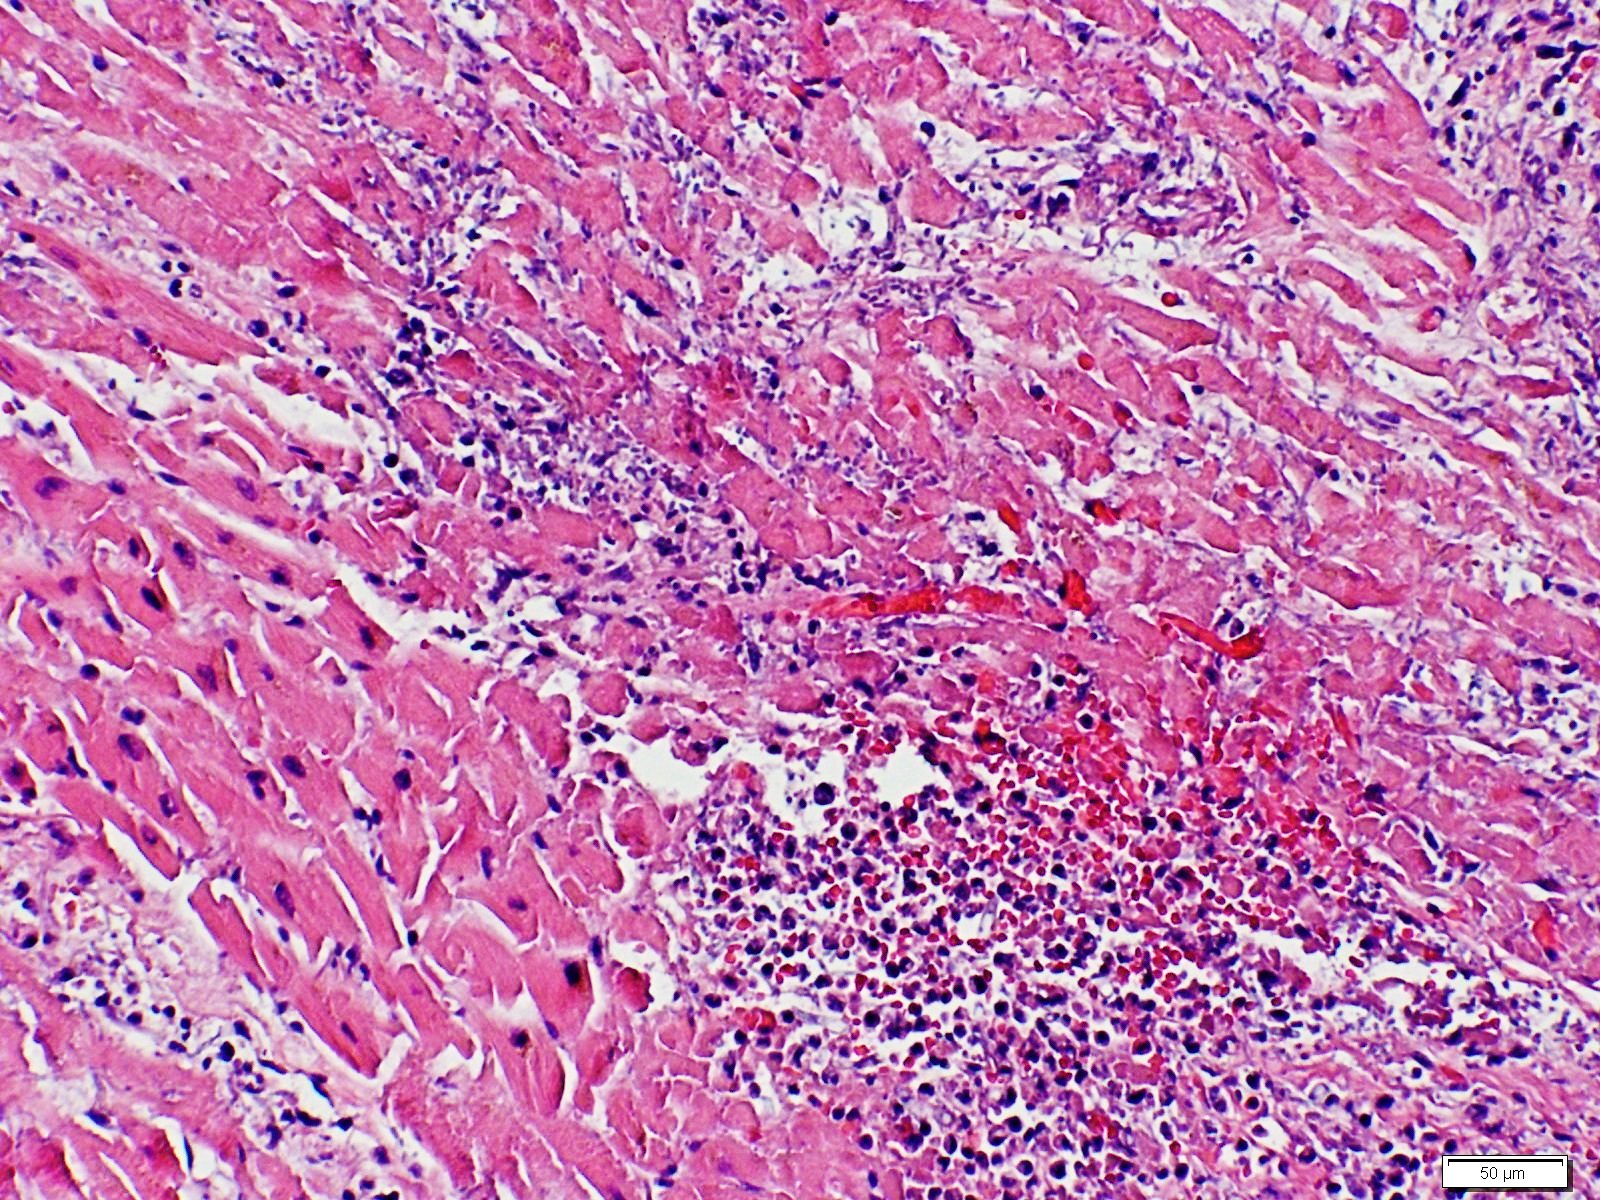

Histology of 44-year-old man with myocardial infarction and HIV demonstrating typical features of MI.